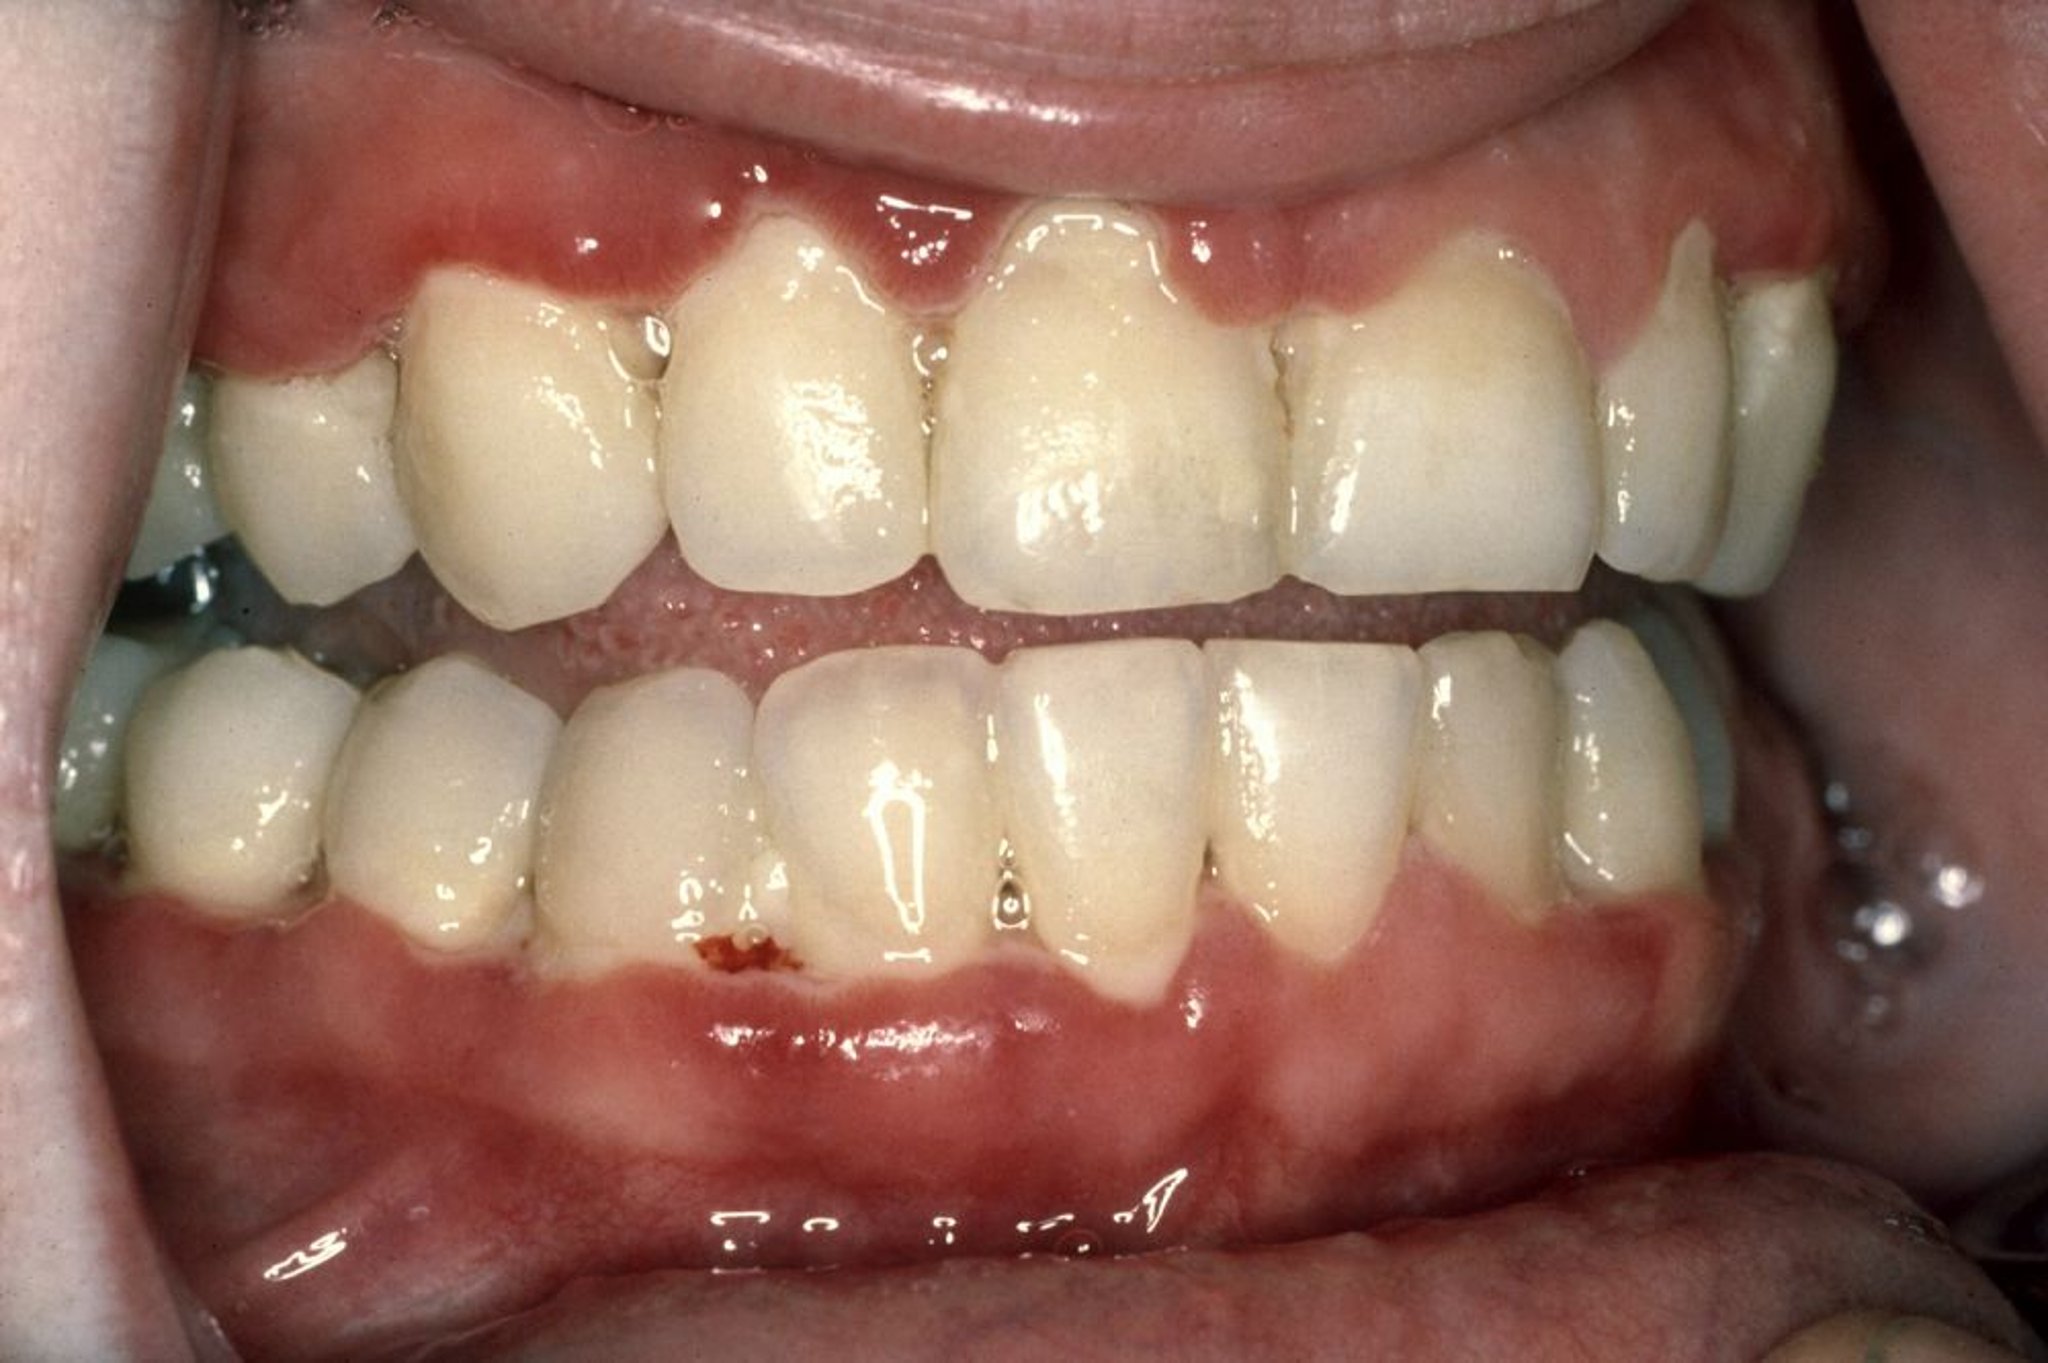

एक्यूट नेक्रोटाइज़िंग अल्सरेटिव जिंजिवाइटिस (ANUG)

आमतौर पर, ANUG की शुरुआत में मसूड़ों में दर्द होता है और खून रिसता है, बहुत ज़्यादा लार बनती है, और कभी-कभी साँस बहुत बदबूदार हो जाती है। लोगों को बुखार भी हो सकता है और उन्हें ऐसा लग सकता है कि वो बीमार हैं। दांतों के बीच मसूड़ों के सिरे पंच्ड आउट (मुक्का मारने से दब गए जैसे) दिखाई देने लगते हैं और छाले (अल्सर) बन जाते हैं जो मृत ऊतक की सलेटी परत से ढके रहते हैं। मसूड़ों से आसानी से खून आने लगता है, और बात करने, खाने और निगलने पर दर्द होता है। अक्सर, जबड़े के नीचे के लिम्फ नोड्स सूज जाते हैं, और हल्का-सा बुखार होता है।